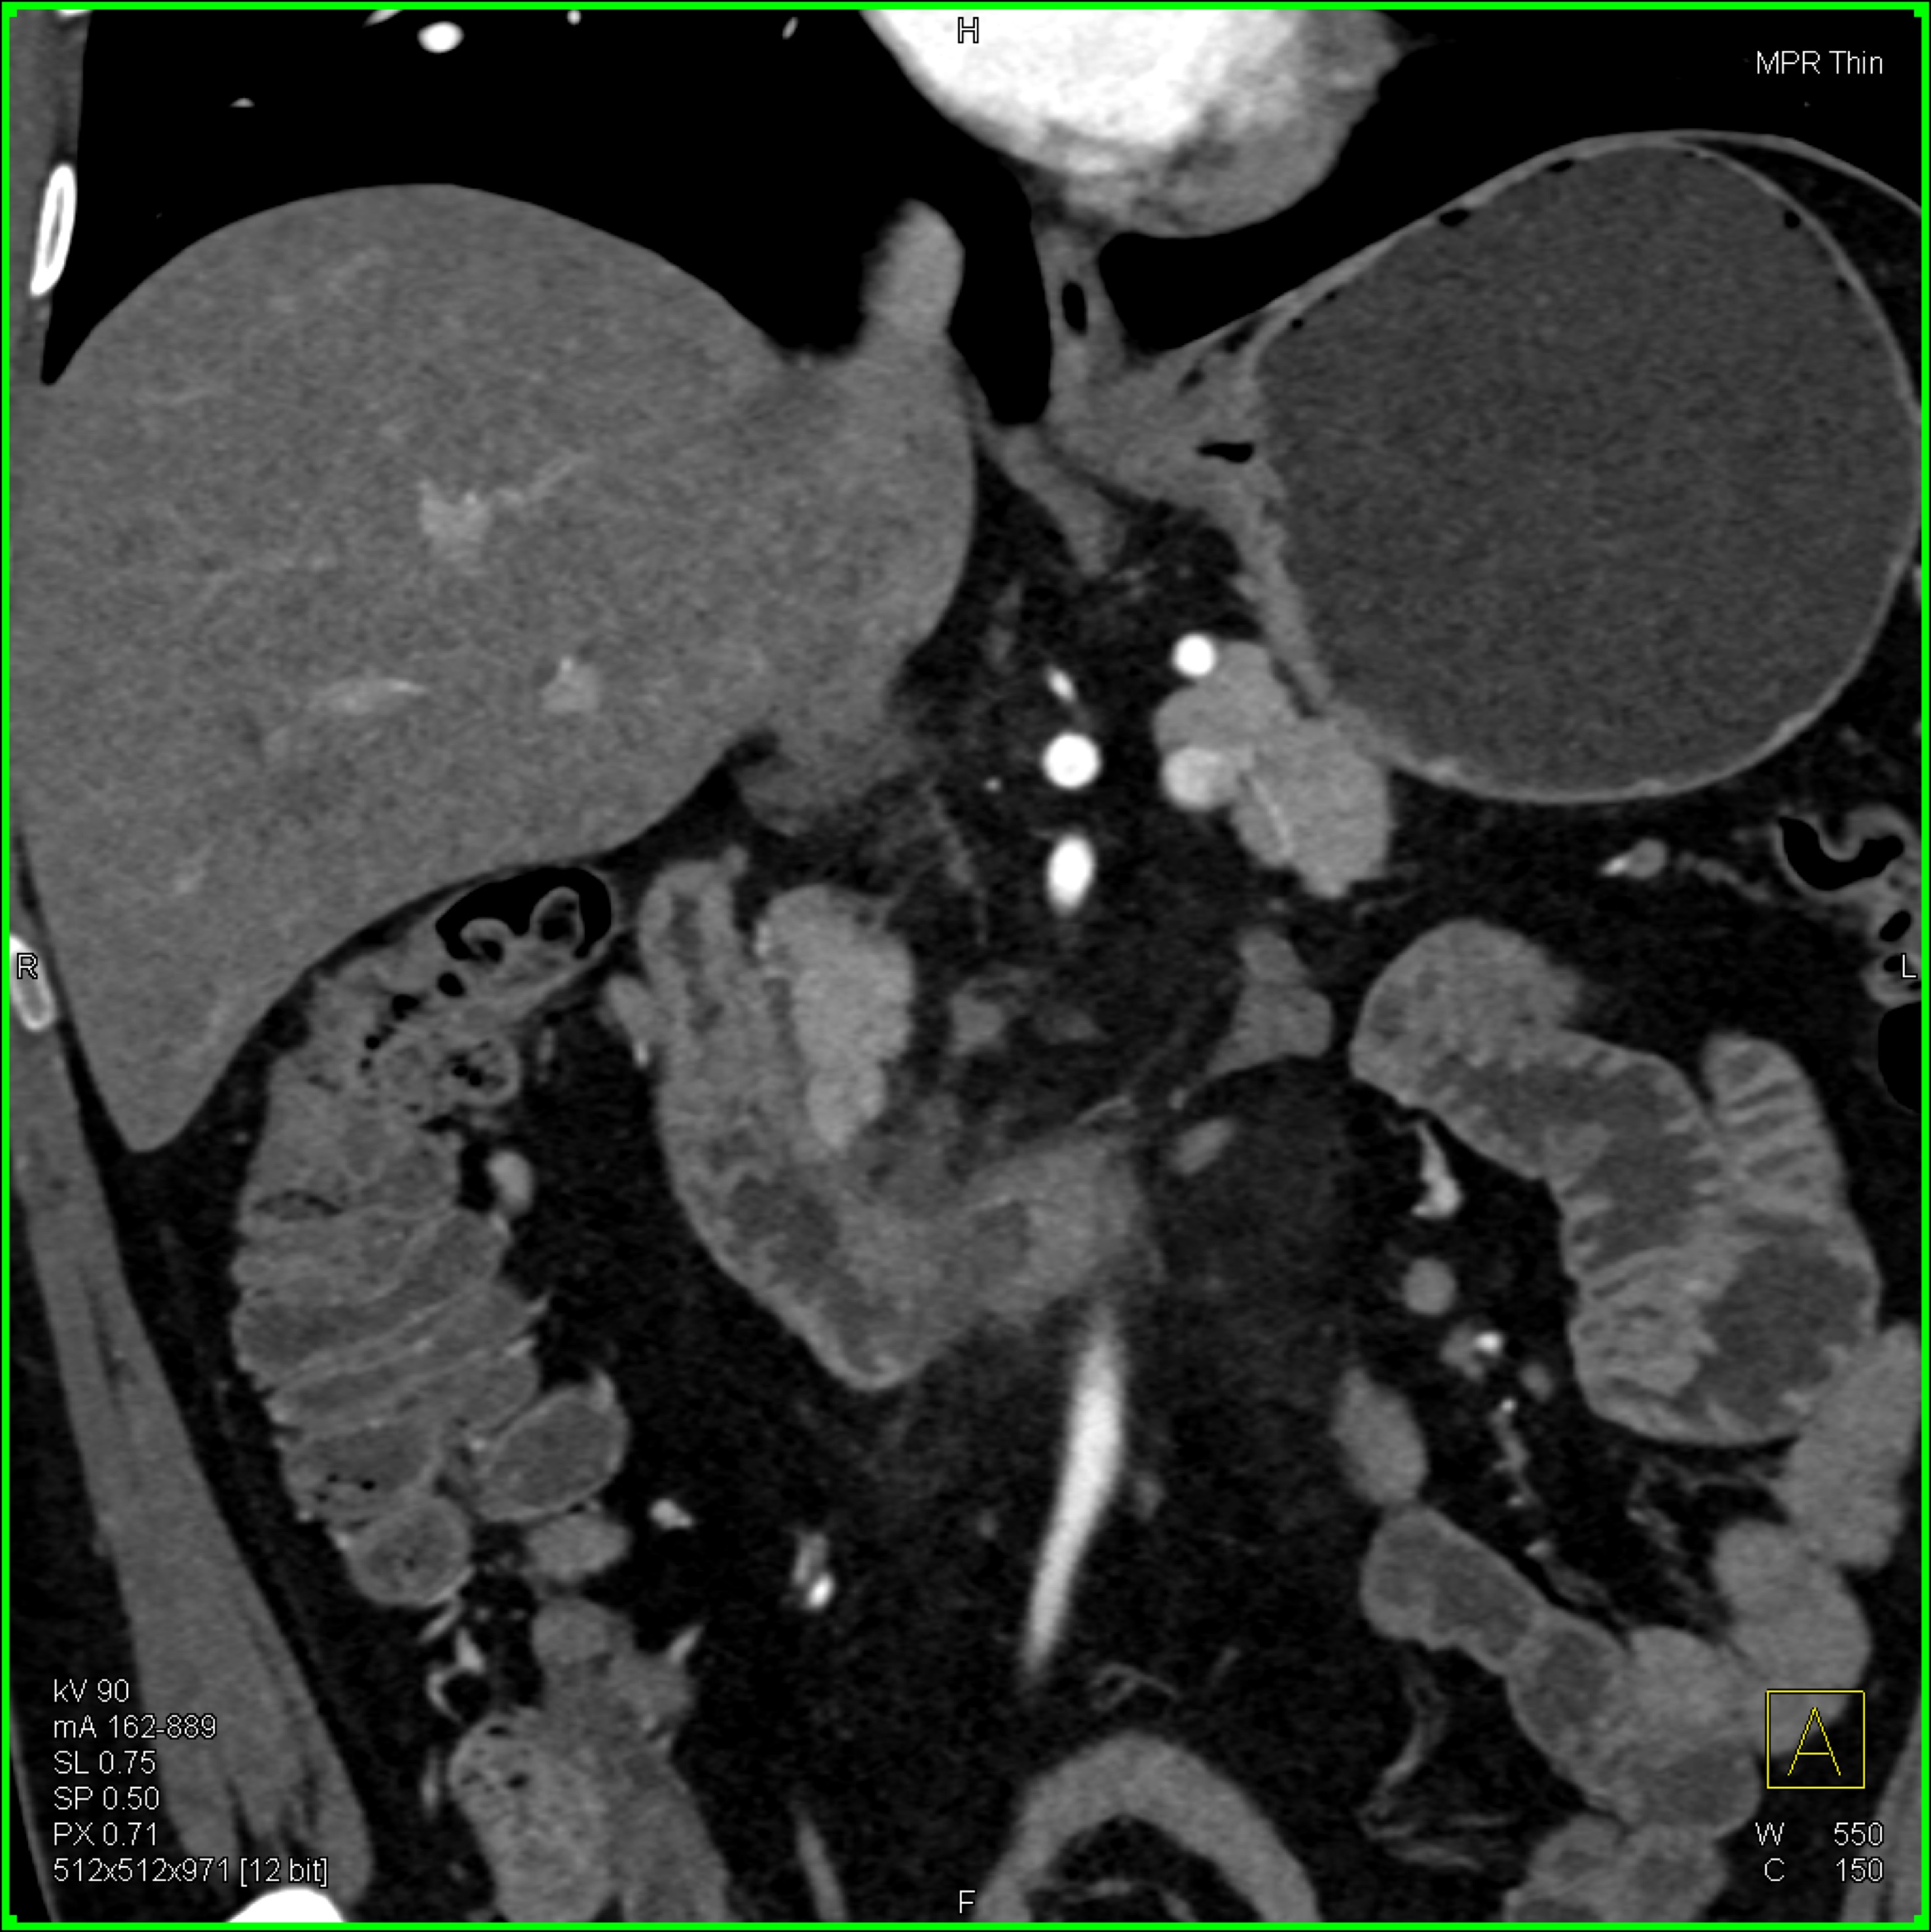

6) The most likely diagnosis in this case is?

lymphoma

acute pyelonephritis

XGP (xanthogranulomatous pyelonephritis)

TB